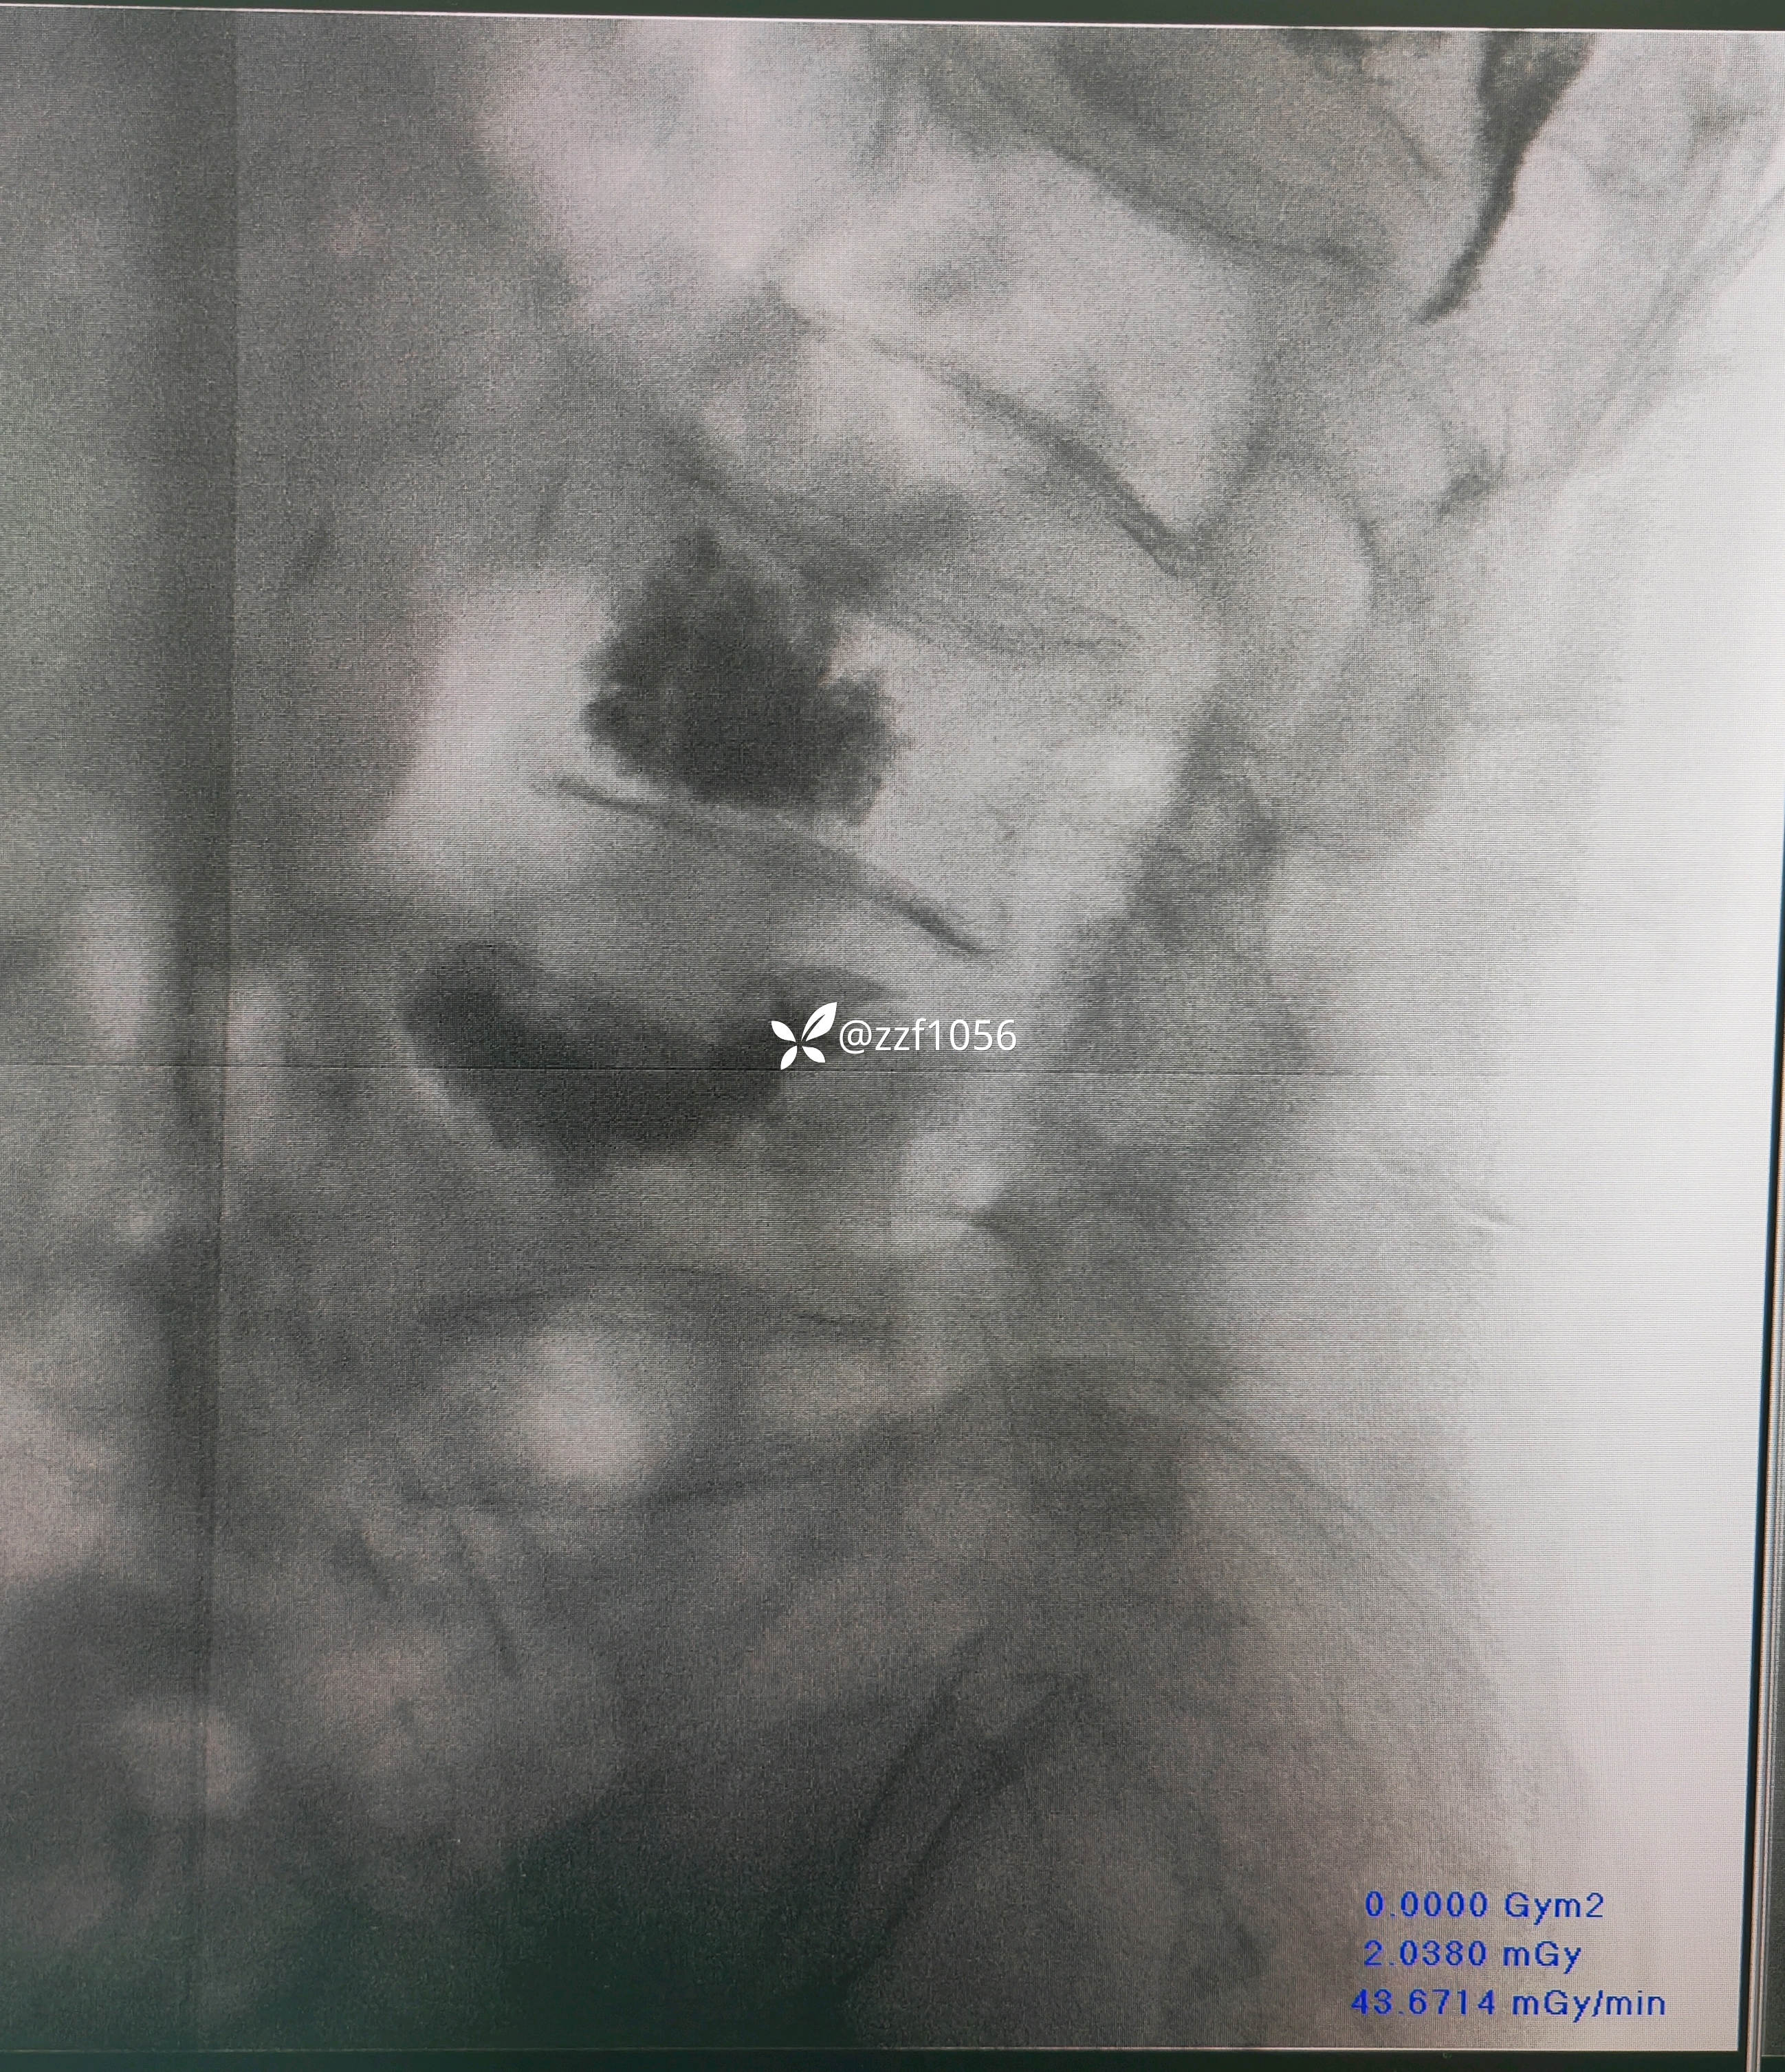

仔细一看这个侧位片,吓我一跳,骨水泥进椎管了?

果不其然,骨水泥渗漏入椎管内,非常能感受到当时主刀惊出一身汗😓,万幸的是患者并没有神经症状。

患者90岁了,单侧穿刺,见好就收,快速收工